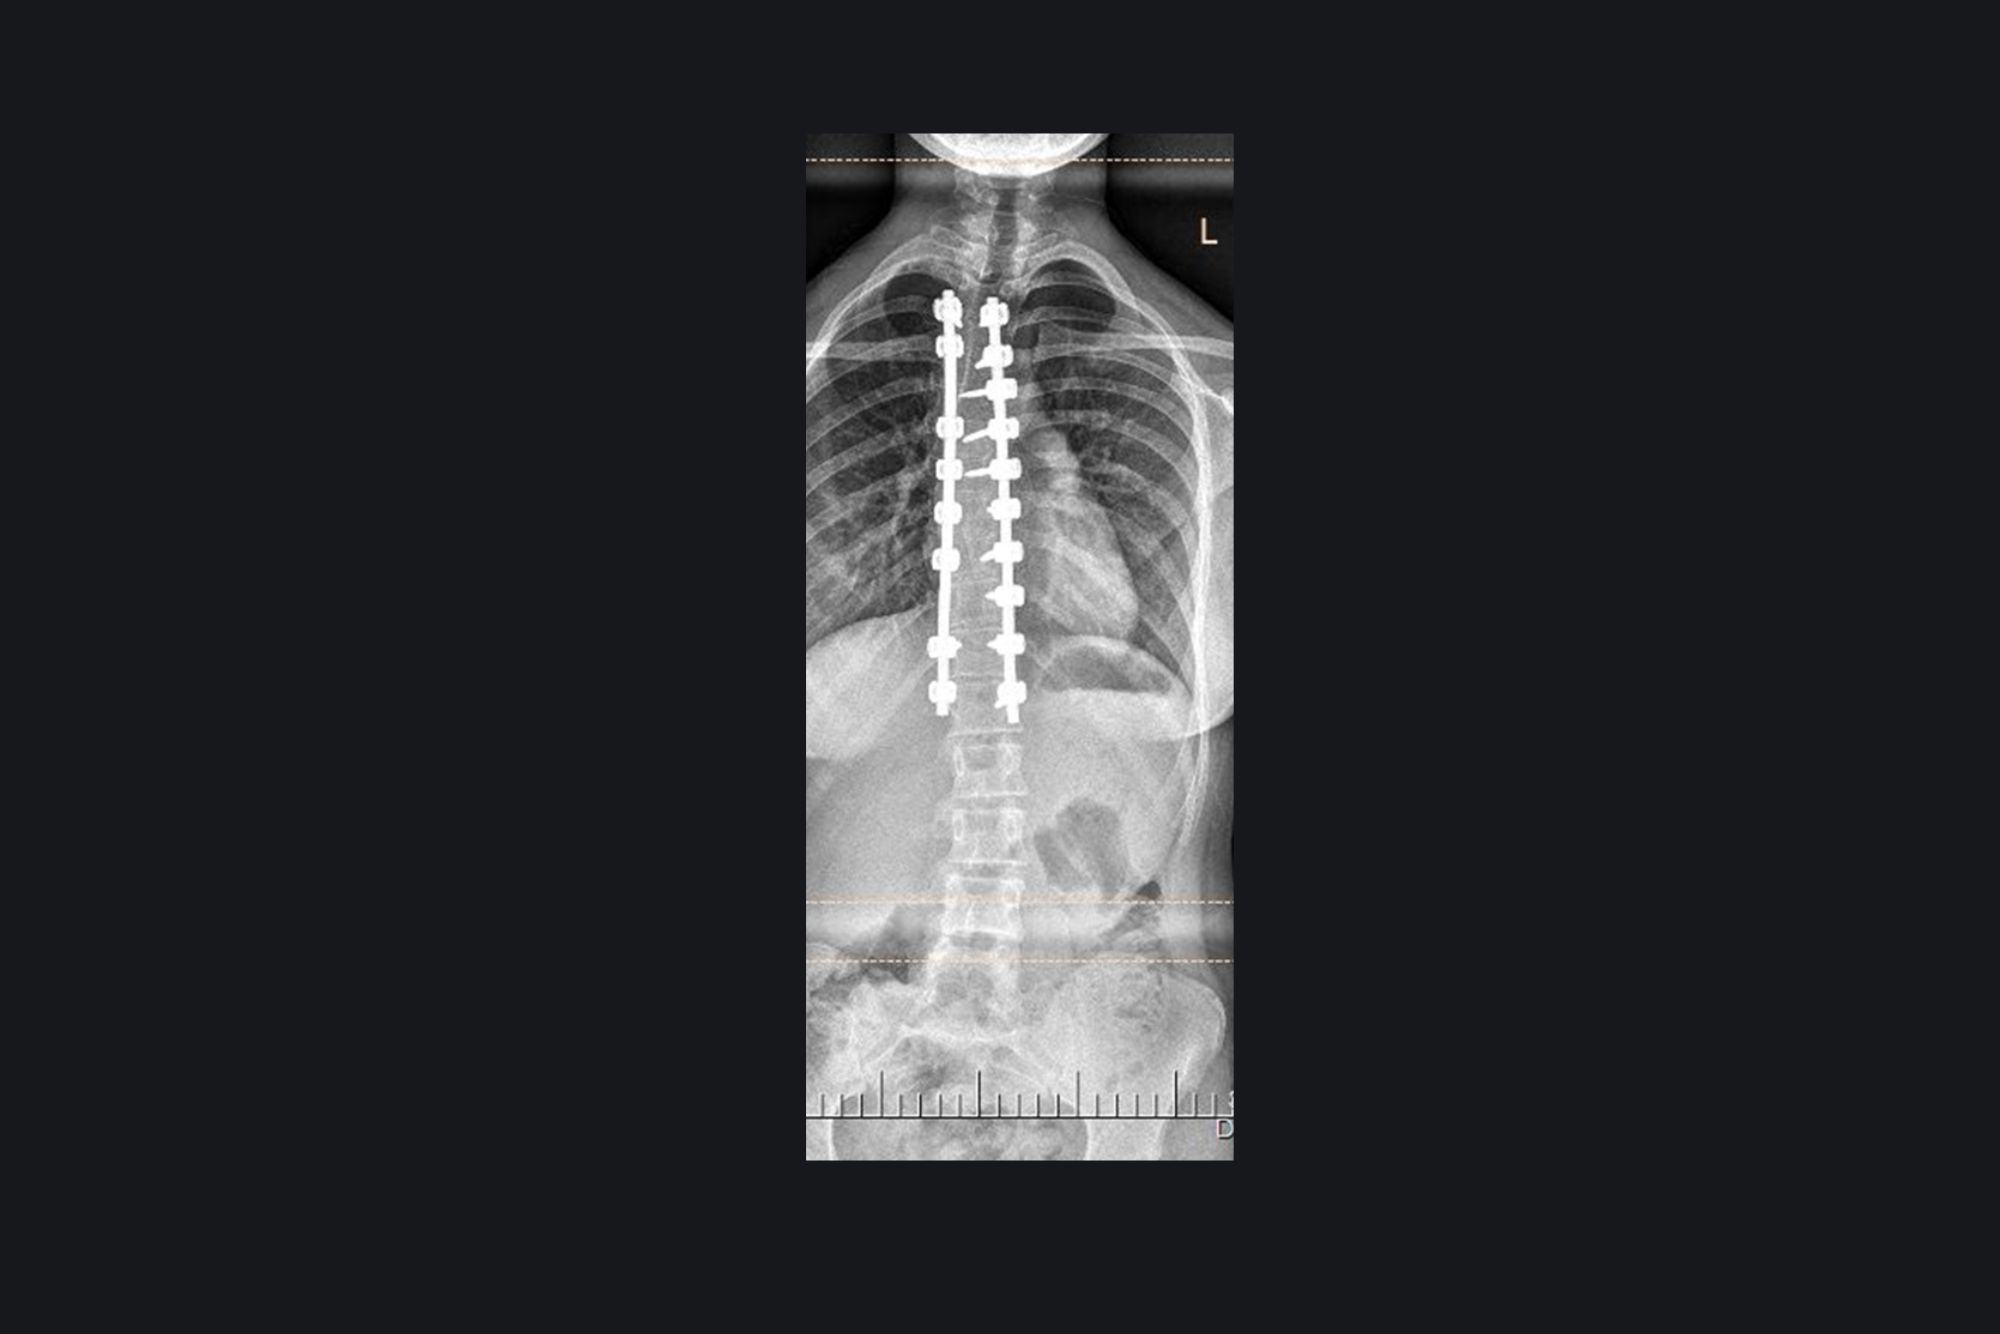

Congenital Scoliosis

PreOperative Image

PostOperative Image